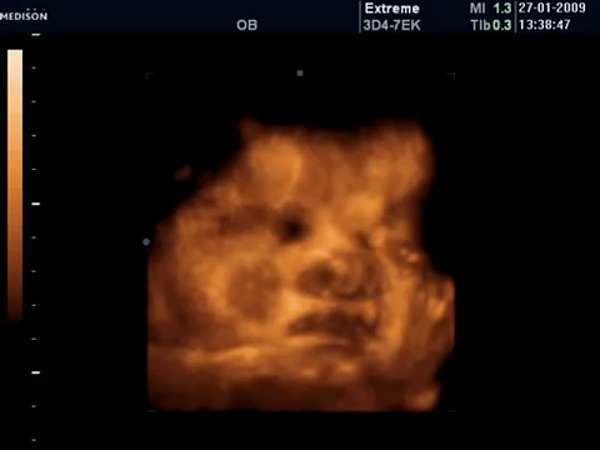

35 Haftalık Bebek

35 haftalık hamilelikte 3d , 4d boyutlu ultrason görüntüsü. 35 hafta gebelik ultrason görüntüleri, 35 haftalık gebelikte anne karnında bebeğin görüntüsü, 35 haftalık ayrıntılı ultrason görüntüsü.